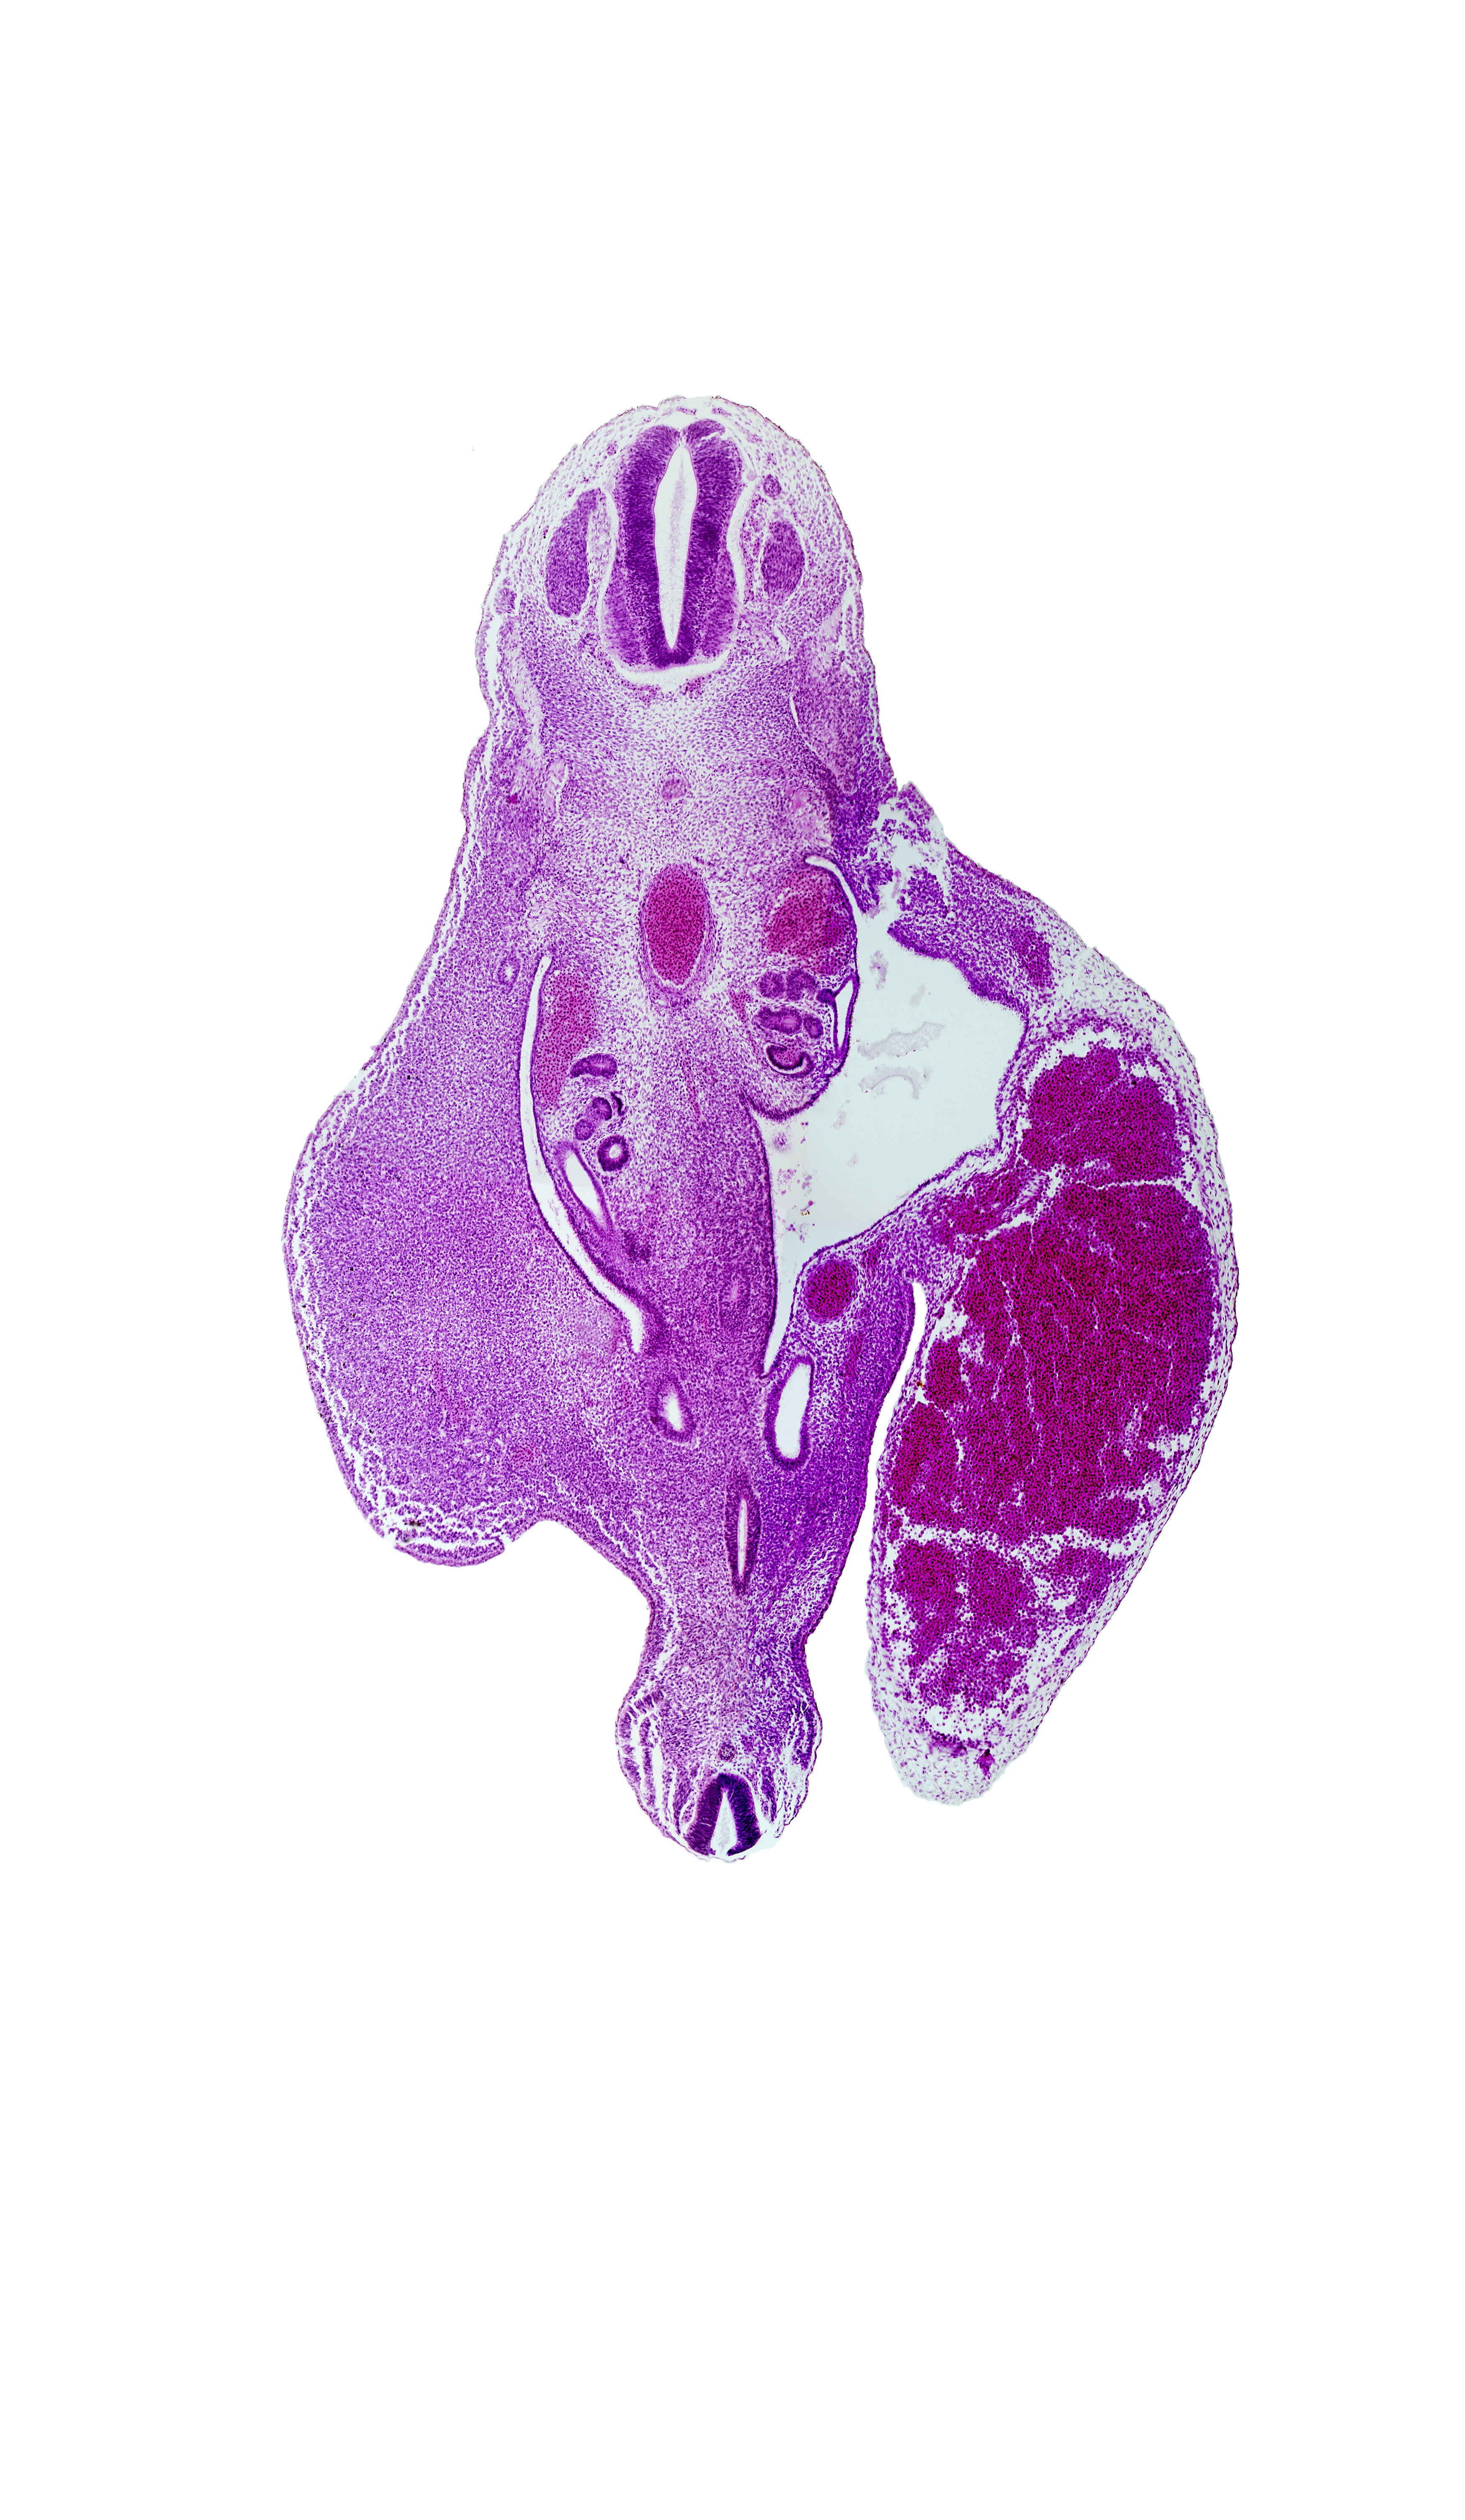

Carnegie Embryo #721 | Location: 23-02-05

Keywords: Co-1 spinal ganglion, T-11 spinal ganglion, aorta, dermatomyotome, hindgut, junction of mesonephric duct and metanephric diverticulum, left umbilical artery, mesonephric duct, notochord

Source: The Virtual Human Embryo.